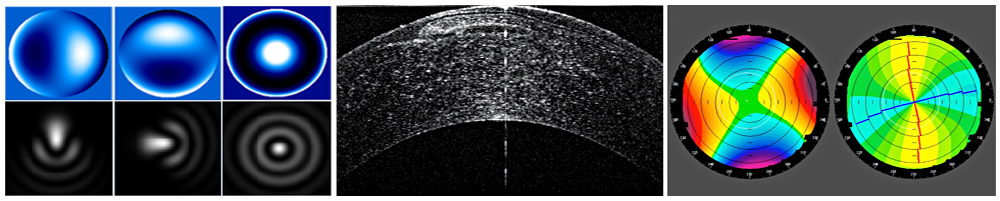

The meeting will focus on laser corneal surgery, machine technology, corneal topography, biomechanics, refractive correction of keratoconus, lens based refractive surgery and phakic IOLs.